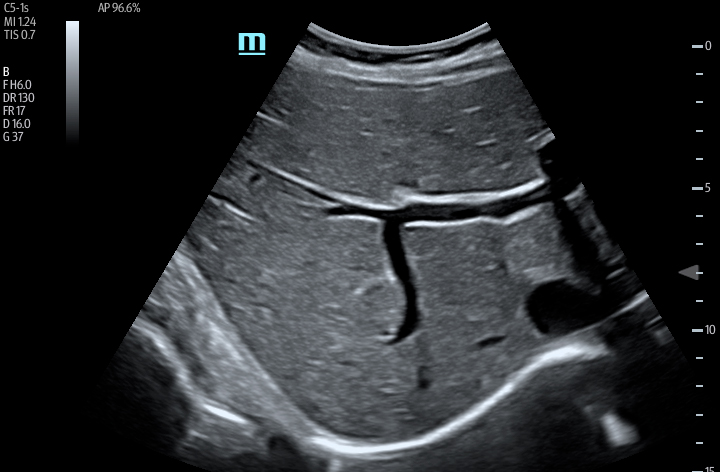

The TE7 Ultrasound System Crystal Series 2.0 is the system of choice from routine point-of-care exams to extreme situations when every second counts. With best-in-class image quality, a sleek form factor, and breakthrough needle visualization advancements, the TE7 System is designed to provide superior performance for rapid, confident exams and procedures in the fast paced, point of care environment.

The TE7 System incorporates an intuitive touchscreen and focused point-of-care protocols designed to standardize and reduce exam times. The System’s second generation iVocal voice recognition technology and new programmable-button transducer technology allows for a hands-free scanning experience, ideal for sterile environments.